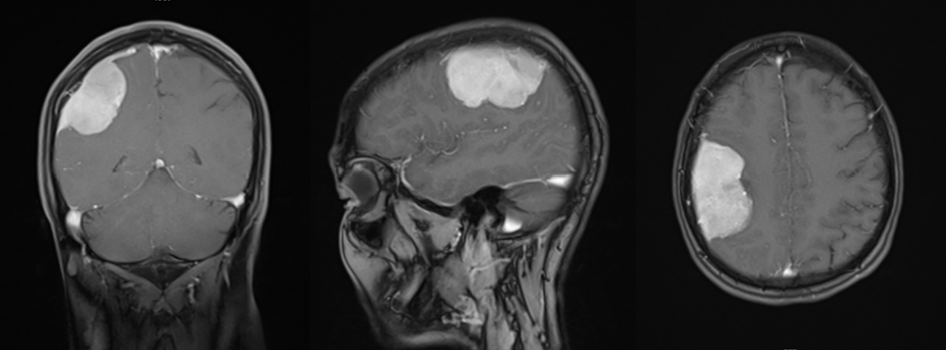

术后核磁增强检查:

入院后我院援疆专家赵明飞主任带领神经外科团队针对患者病情进行分析,入院后检查、结合患者影像学特点、查体及既往病史,初步考虑患者颅内病变为巨大功能区脑膜瘤。需及早行手术切除肿瘤,以缓解肿瘤对神经纤维束的压迫,减少对功能区脑组织损伤,积极争取使患者肢体功能最大恢复。此患者脑肿瘤位于右侧大脑功能区,开颅手术过程中若损伤功能区脑组织,将会造成永久性不可逆的神经功能缺损,出现肢体活动障碍。赵明飞主任应用神经导航联合术中黄荧光成像技术完成肿瘤的精准切除,完美保护脑功能。手术顺利结束。术后月热尼沙的头痛症状随即就得到了改善,肢体功能无影响,复查头部CT及MR提示脑肿瘤完整切除,效果满意。

术后磁共振:肿瘤完整切除